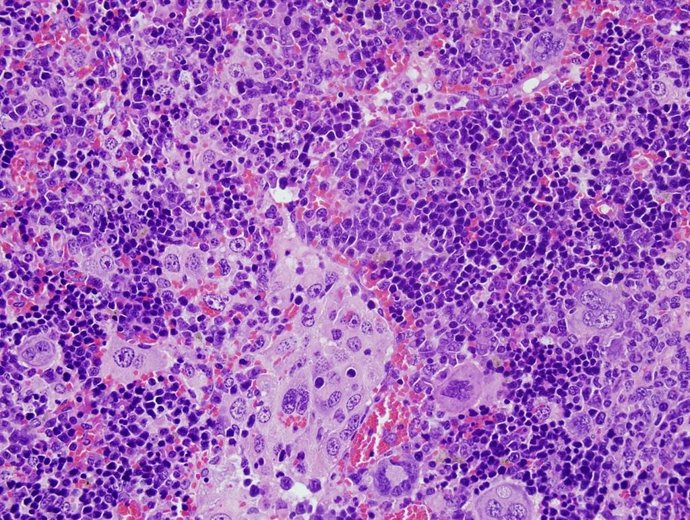

Archivo - Imagen de microscopia de un linfoma desarrollado por ratones con alteraciones en el gen VAV1.

Archivo - Imagen de microscopia de un linfoma desarrollado por ratones con alteraciones en el gen VAV1. - XOSÉ R. BUSTELO - Archivo